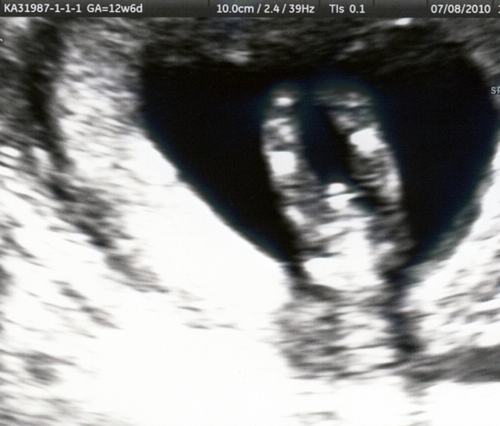

28 July 2010

Oh Baby! Here are some of our first photos:

us_2

yep, we're having a boy!